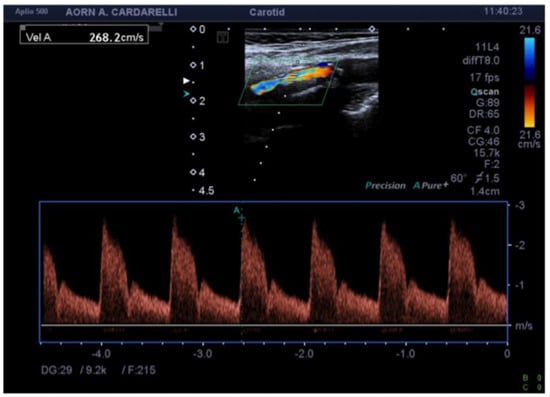

4. Color-Doppler Ultrasound (CDUS)

- Qiu, Y.; Dong, Y.; Mao, F.; Zhang, Q.; Yang, D.; Chen, K.; Shi, S.; Zuo, D.; Tian, X.; Yu, L.; et al. High-Frame Rate Vector Flow Imaging Technique: Initial Application in Evaluating the Hemodynamic Changes of Carotid Stenosis Caused by Atherosclerosis. Front. Cardiovasc. Med. 2021, 8, 617391. [Google Scholar] [CrossRef] [PubMed]

- Murray, C.S.G.; Nahar, T.; Kalashyan, H.; Becher, H.; Nanda, N.C. Ultrasound assessment of carotid arteries: Current concepts, methodologies, diagnostic criteria, and technological advancements. Echocardiography 2018, 35, 2079–2091. [Google Scholar] [CrossRef]

- Grajo, J.R.; Barr, R.G. Duplex Doppler Sonography of the Carotid Artery: Velocity Measurements in an Artery With Contralateral Stenosis. Ultrasound Q. 2007, 23, 199–202. [Google Scholar] [CrossRef] [PubMed]